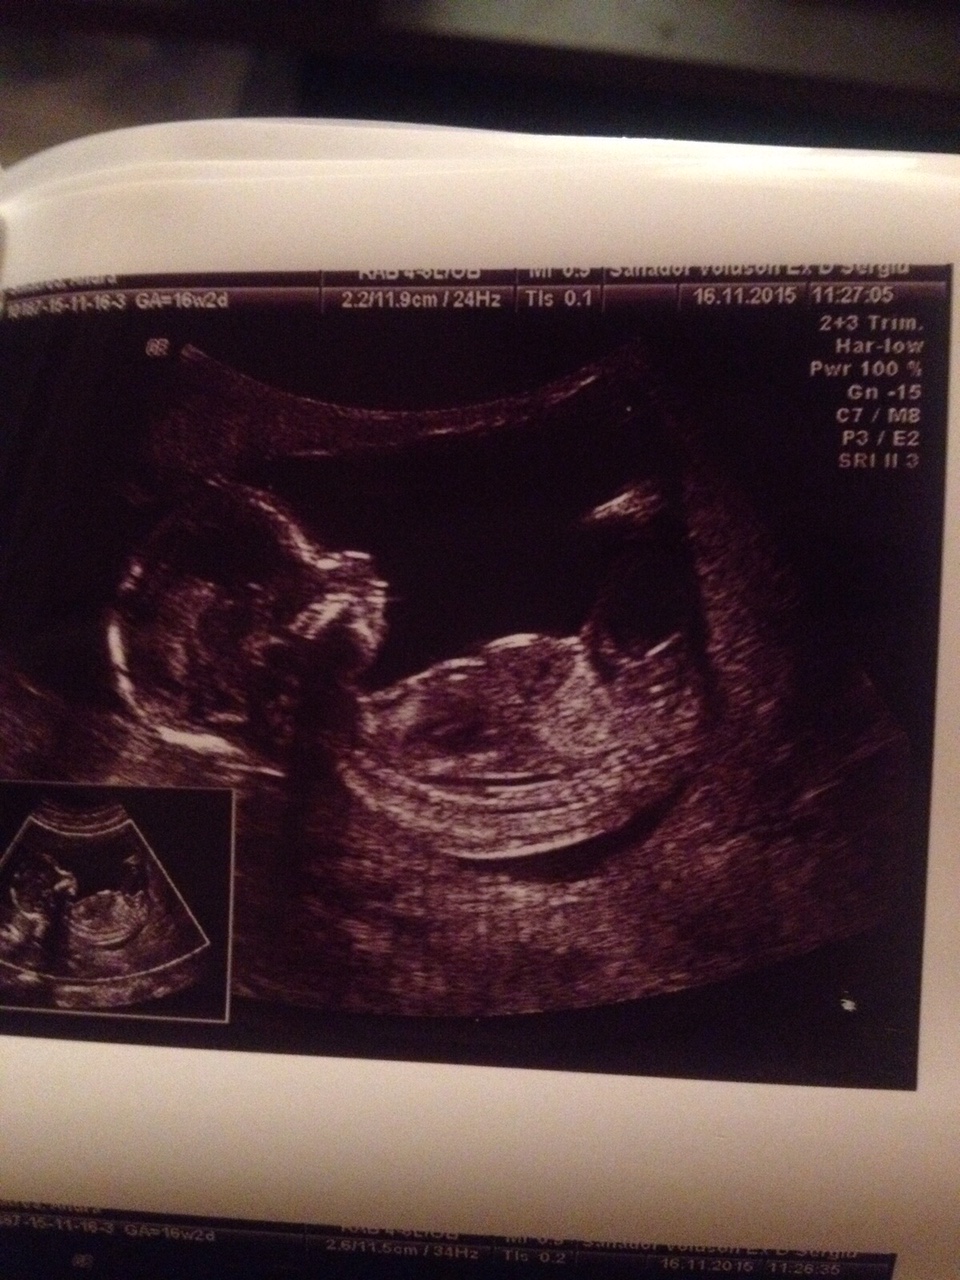

Girl? 26 weeks long now....help

Hi ladies. I am having a very upset friend that stays outside town. She is 26 weeks now and she got girl boy boy girl prediction until now from 2 different doctors. Unfortunatelly she couldnt come to our hospital to predict the correct gender for her and she is very curious to find out what she is having..its her first child and it dosent matter really but just so she can know what color to buy :)))

I said girl but not sure either. So I am attaching here a few pictures. Hope someone can help.

Attachment 29712Attachment 29713